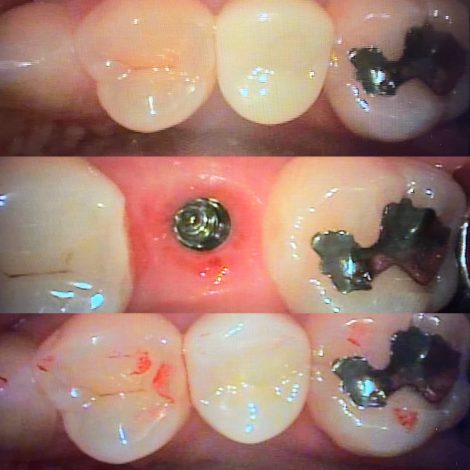

写真は、

仮歯→歯茎の形態が整った状態→最終のセラミックが入った状態

根が割れて抜歯したのち、インプラント埋入を行い、骨との結合期間が経過した後で、インプラント用の仮歯を入れました

この作業をコストカットの為に省く先生もいますが、歯茎の形態を整える、つまりは歯茎への最終補綴物の適合を考えると必要な処置になります

州デンタルオフィスでは可能な限りセメント固定ではなく、スクリュー固定のネジ止めタイプを選択します

理由は、インプラントのメンテナンスと修理のしやすさ、また、セメントの取り残しを防ぐためです